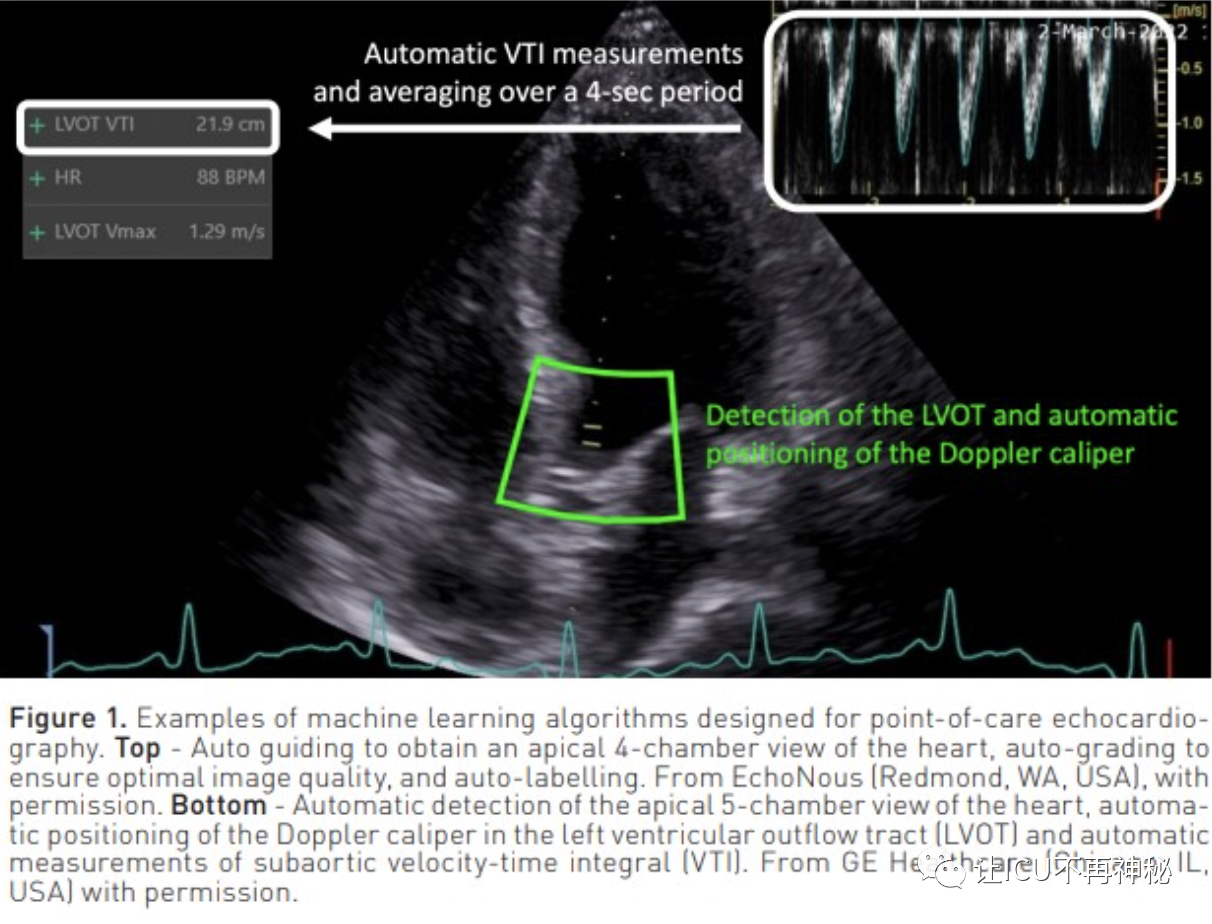

人工智能與治療點(diǎn)超聲心動(dòng)圖已經(jīng)訓(xùn)練了幾種ML算法來(lái)識(shí)別心臟圖像,并引導(dǎo)用戶正確握住和定位他們的經(jīng)胸探頭。這樣的算法還能夠?qū)D像質(zhì)量進(jìn)行分級(jí)并標(biāo)記心臟結(jié)構(gòu)。圖1中顯示了一個(gè)示例。一些ML算法可以自動(dòng)進(jìn)行超聲心動(dòng)圖測(cè)量。例如,autoVTI算法可以識(shí)別心臟的5腔心尖視圖,在左心室流出道中自動(dòng)定位脈搏波多普勒卡尺,并在短時(shí)間窗口內(nèi)記錄主動(dòng)脈下速度時(shí)間積分(VTI)(圖1)。最近的一項(xiàng)臨床評(píng)估表明,autoVTI算法可以幫助受訓(xùn)者像超聲心動(dòng)圖專家一樣高效地使用超聲波估計(jì)VTI、腦卒中量(SV~VTI x Pi)和心輸出量。還開(kāi)發(fā)了幾種ML算法用于左心室射血分?jǐn)?shù)(LVEF)的自動(dòng)估計(jì)。比較研究表明,與專家手動(dòng)測(cè)量相比,它們可以使新手更準(zhǔn)確、更具再現(xiàn)性地測(cè)量LVEF。其他超聲算法已被設(shè)計(jì)為通過(guò)下腔靜脈呼吸變化的自動(dòng)量化來(lái)預(yù)測(cè)機(jī)械通氣患者的流體反應(yīng)性,或通過(guò)肺B線的自動(dòng)量化檢測(cè)肺水腫。總之,ML算法在幫助新手進(jìn)行治療點(diǎn)超聲心動(dòng)圖評(píng)估方面的價(jià)值已在幾項(xiàng)臨床研究中得到證明。然而,鑒于接受過(guò)超聲心動(dòng)圖培訓(xùn)的重癥監(jiān)護(hù)醫(yī)生的比例正在急劇增加,人工智能創(chuàng)新是否有必要增加超聲血流動(dòng)力學(xué)評(píng)估的數(shù)量和質(zhì)量仍有待確定。